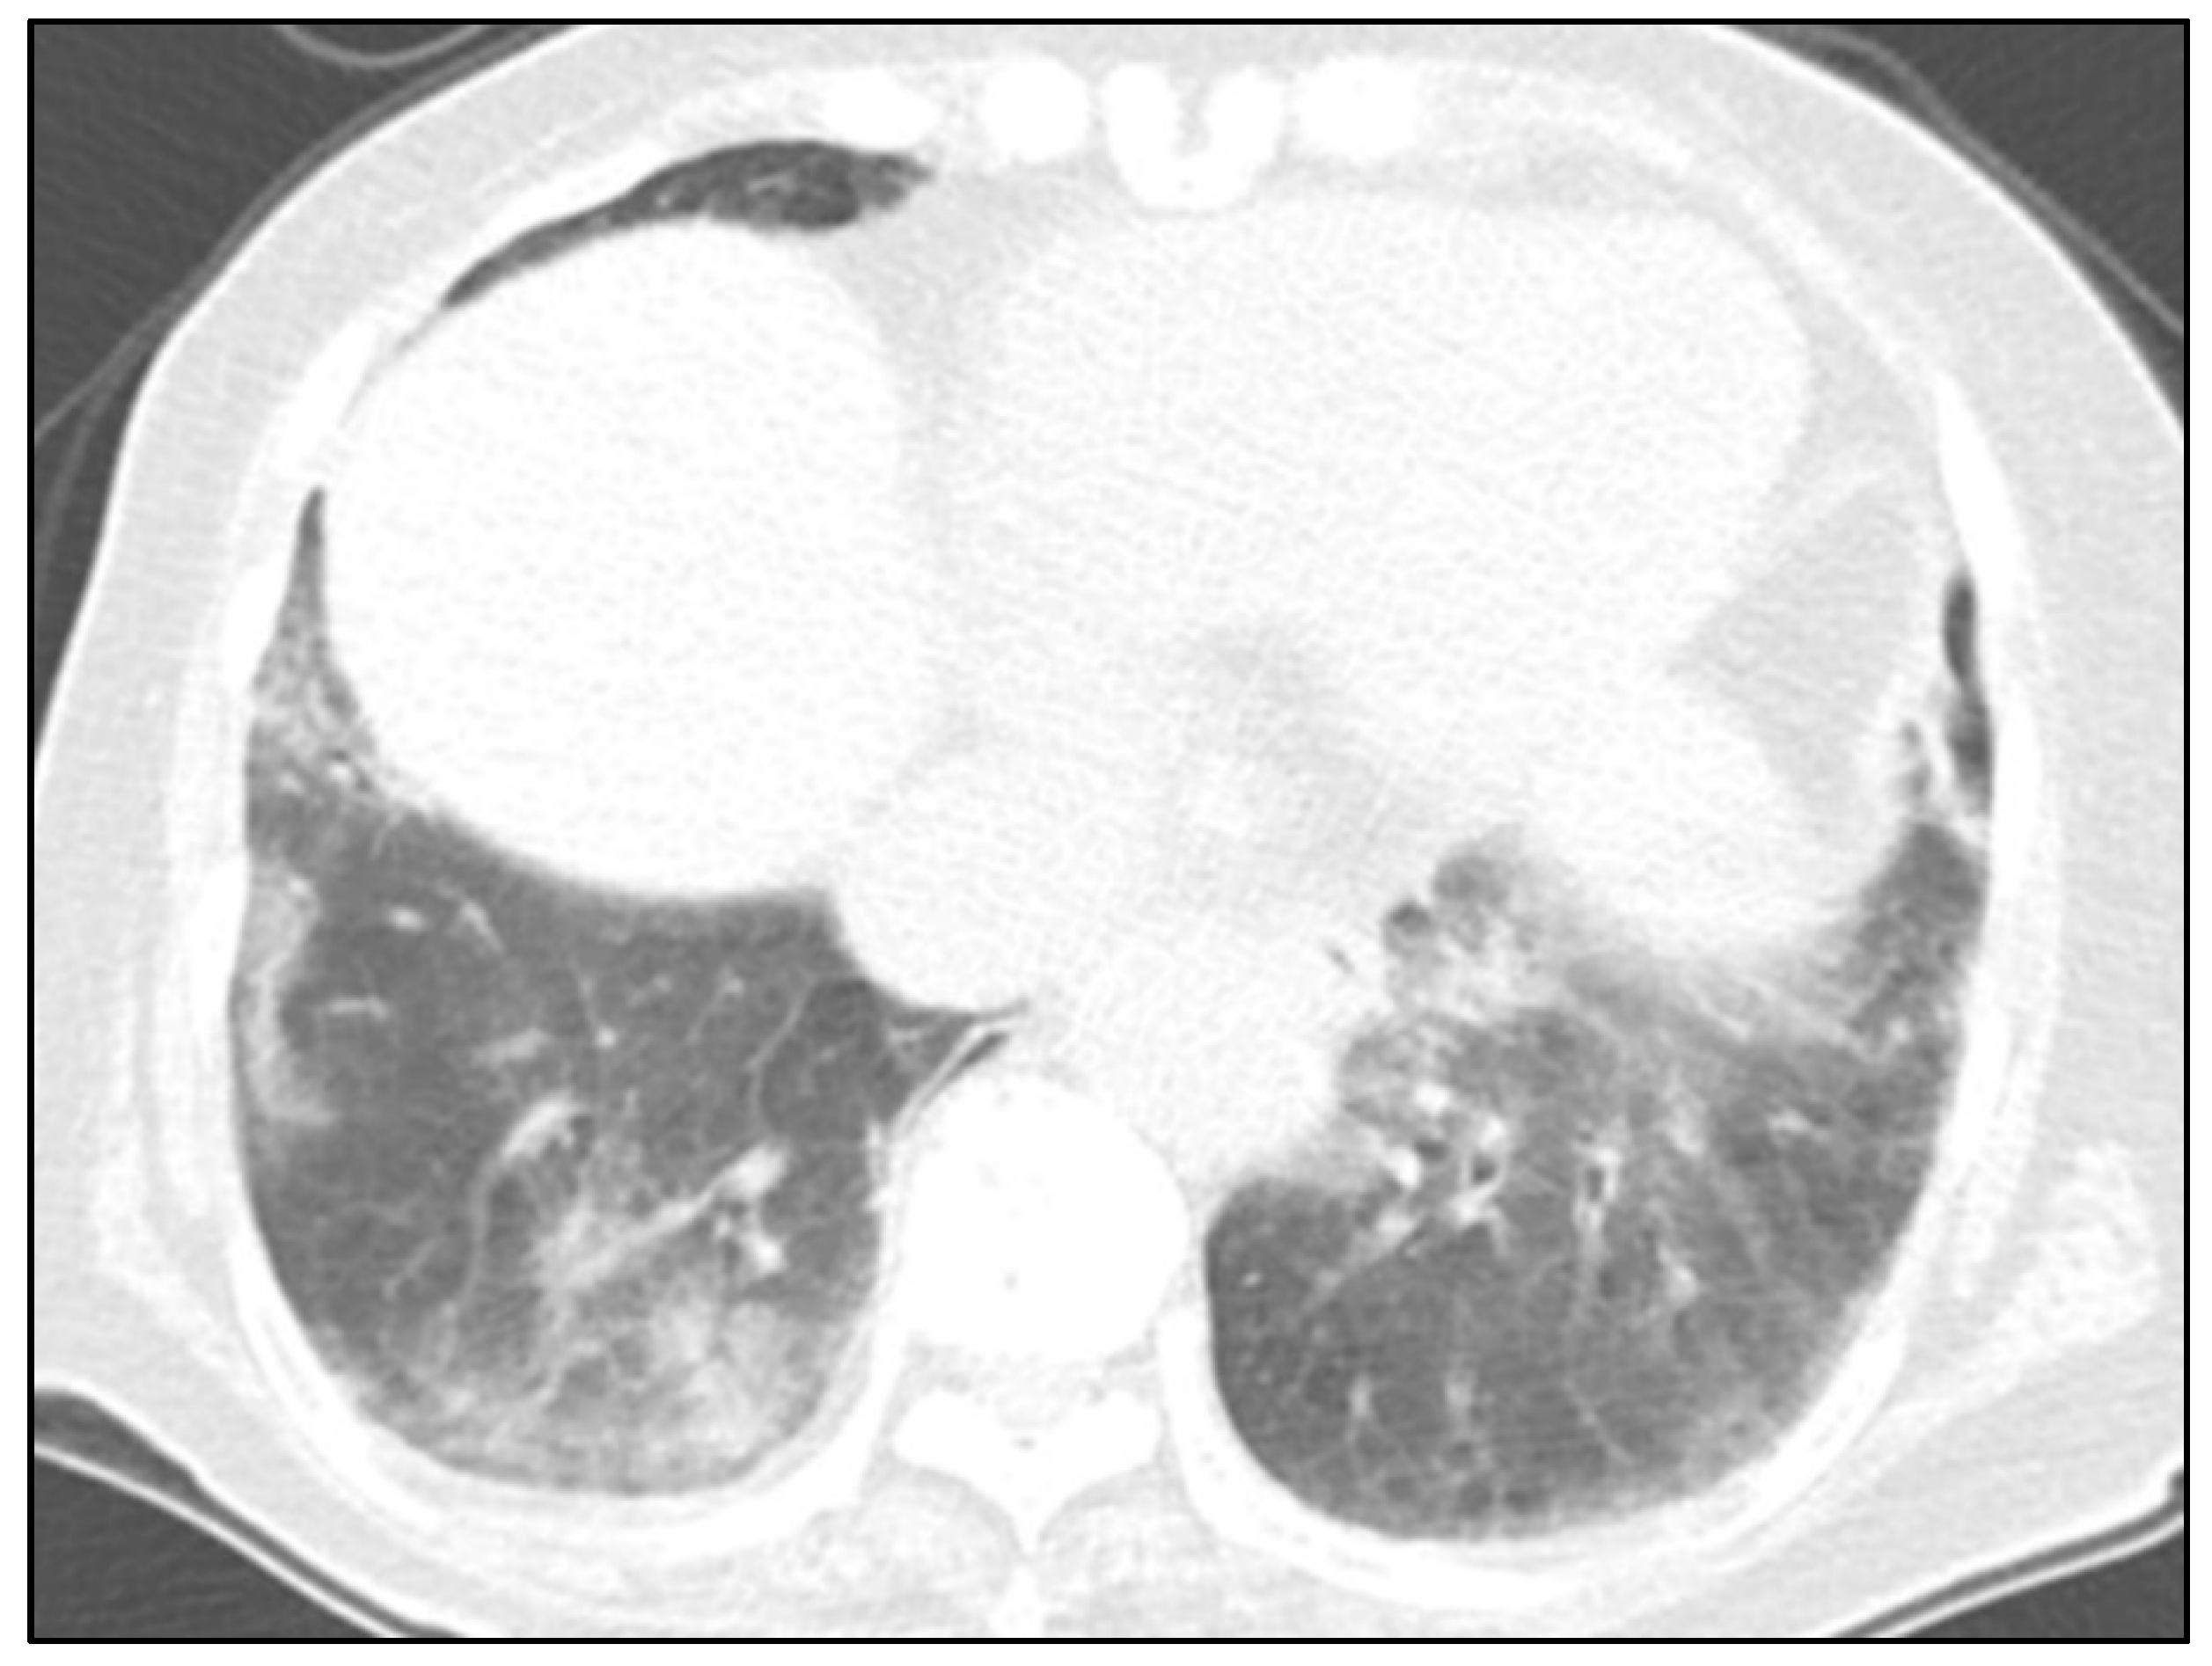

2. Case Report